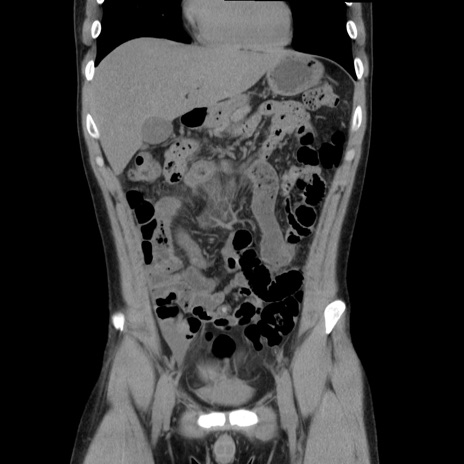

症例36(冠状断像)

【症例】20歳代 男性

【主訴】心窩部痛

【現病歴】今朝より上腹部痛あり。一旦軽快していたが再度出現したため救急要請。昨日夕に白身の魚を含む刺身を食べた。

【身体所見】BP 136/89mmHg、HR 74/min、BT 37.0℃、腹部:膨満、軟、心窩部に圧痛あり。反跳痛なし、筋性防御なし、腸雑音やや亢進あり。

【データ】WBC 17700、CRP 0.48